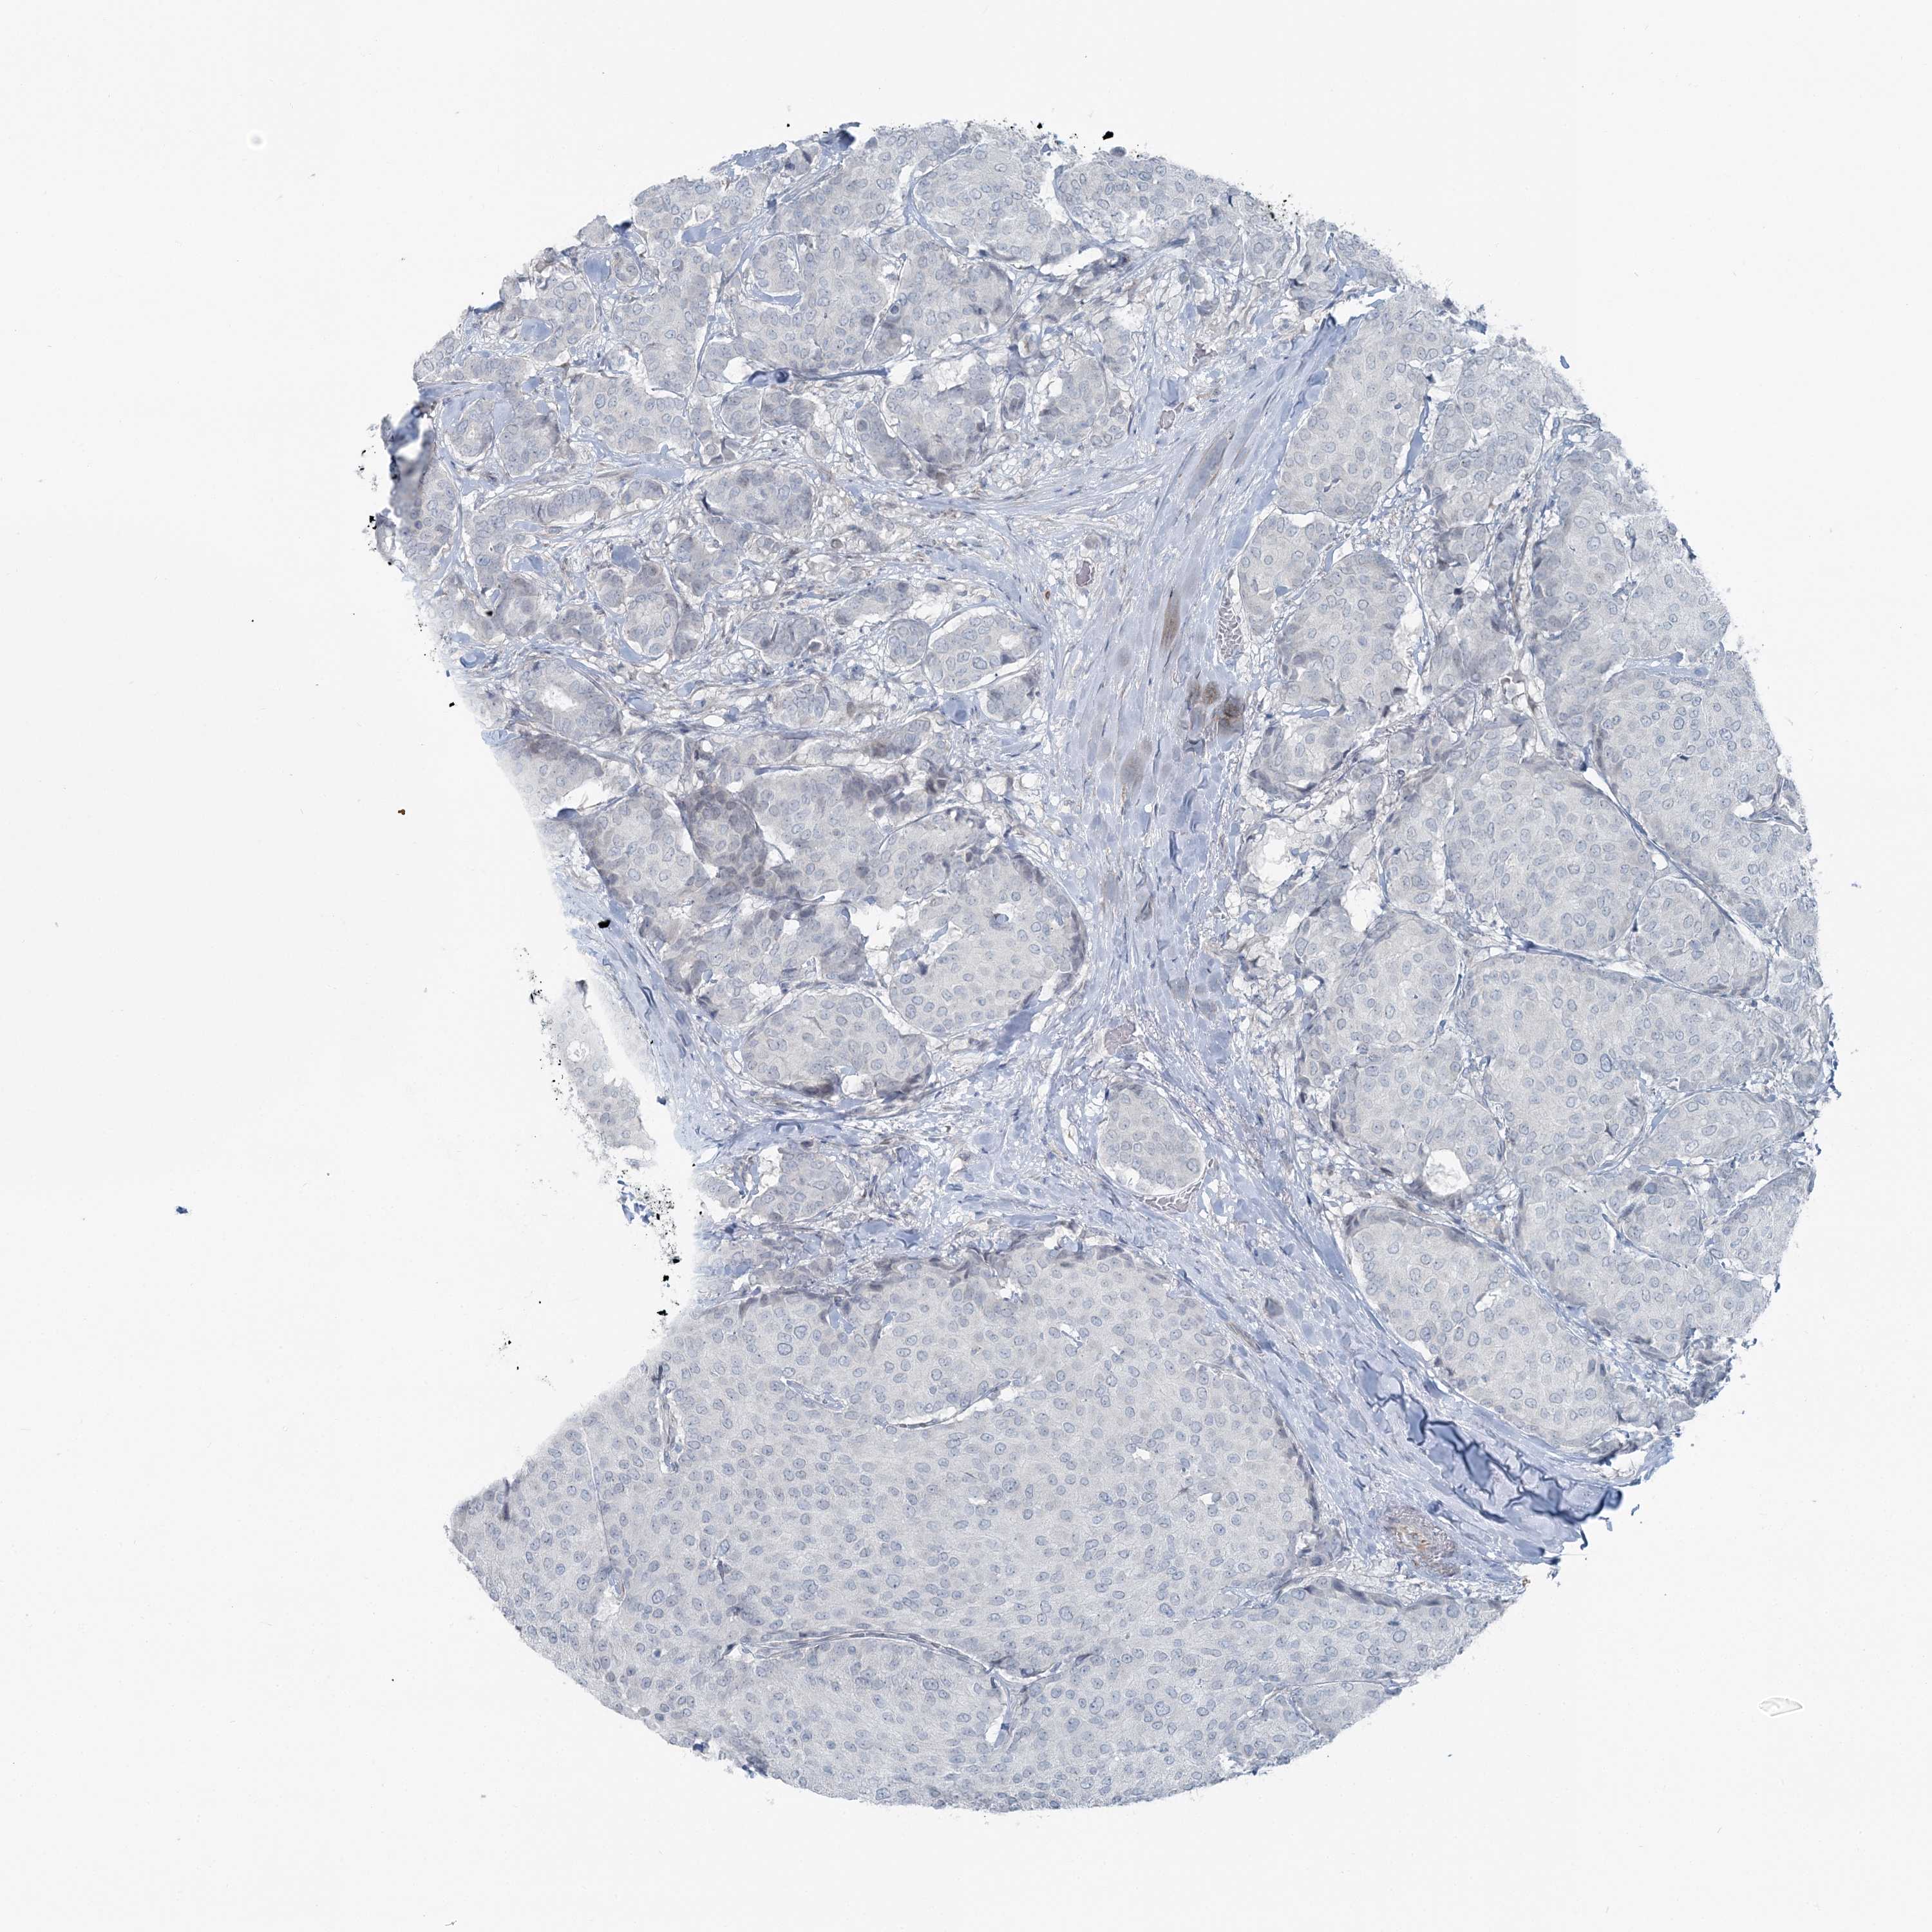

CANCER BREAST CANCER Show tissue menu

BRCA TCGA BRCA VALIDATION PROTEIN EXPRESSION

ANTIBODIES

AND

VALIDATION